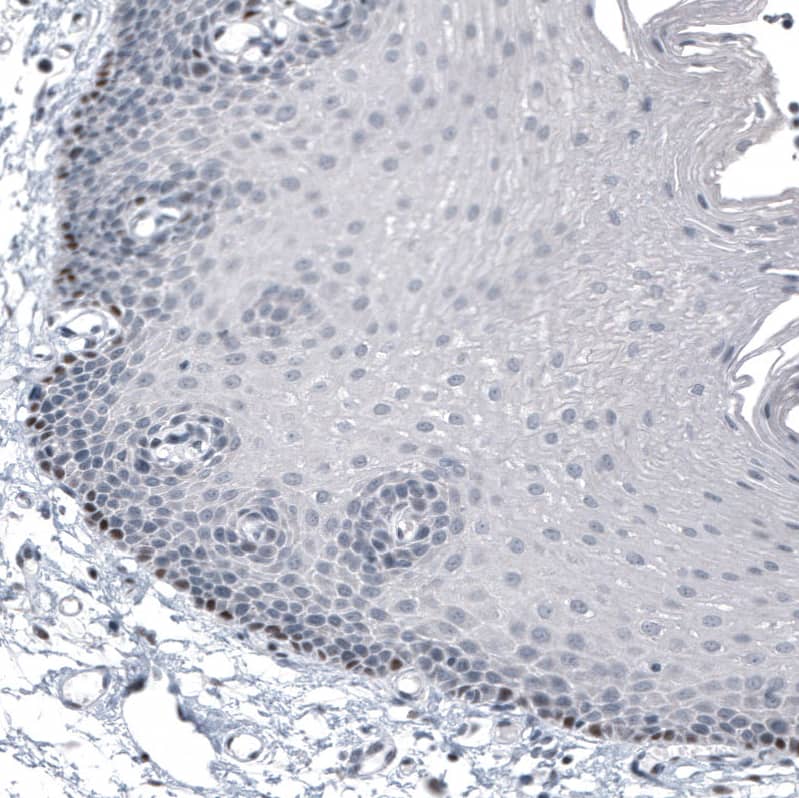

Staining of human squamous epithelium shows strong nuclear positivity in stratum basale cells.